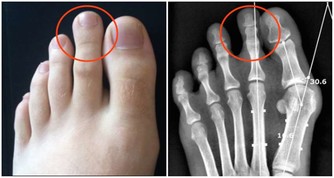

- 與某些疾病的相關性:HDL過高可能與肝臟疾病、腎臟疾病或癌症風險增加有潛在關聯,但相關機制尚待進一步研究。